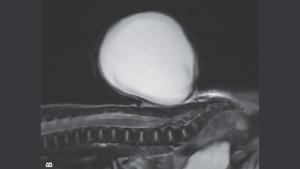

diverse „Baloanele roșii” înmuguresc din spatele bebelușului din cauza unui defect congenital 10 ianuarie 2025 by Echipa Club S&T | Leave a Comment Sacul sub formă de balon de țesut și lichid care a crescut din coloana vertebrală a bebelușului, prezentat pe o scanare prin rezonanță magnetică (RMN). (Credit imagine: The New England Journal of Medicine ©2024) Un defect congenital obișnuit a făcut ca un nou-născut să dezvolte un sac uriaș, roșu, asemănător unui balon, care ieșea din […] Read more »